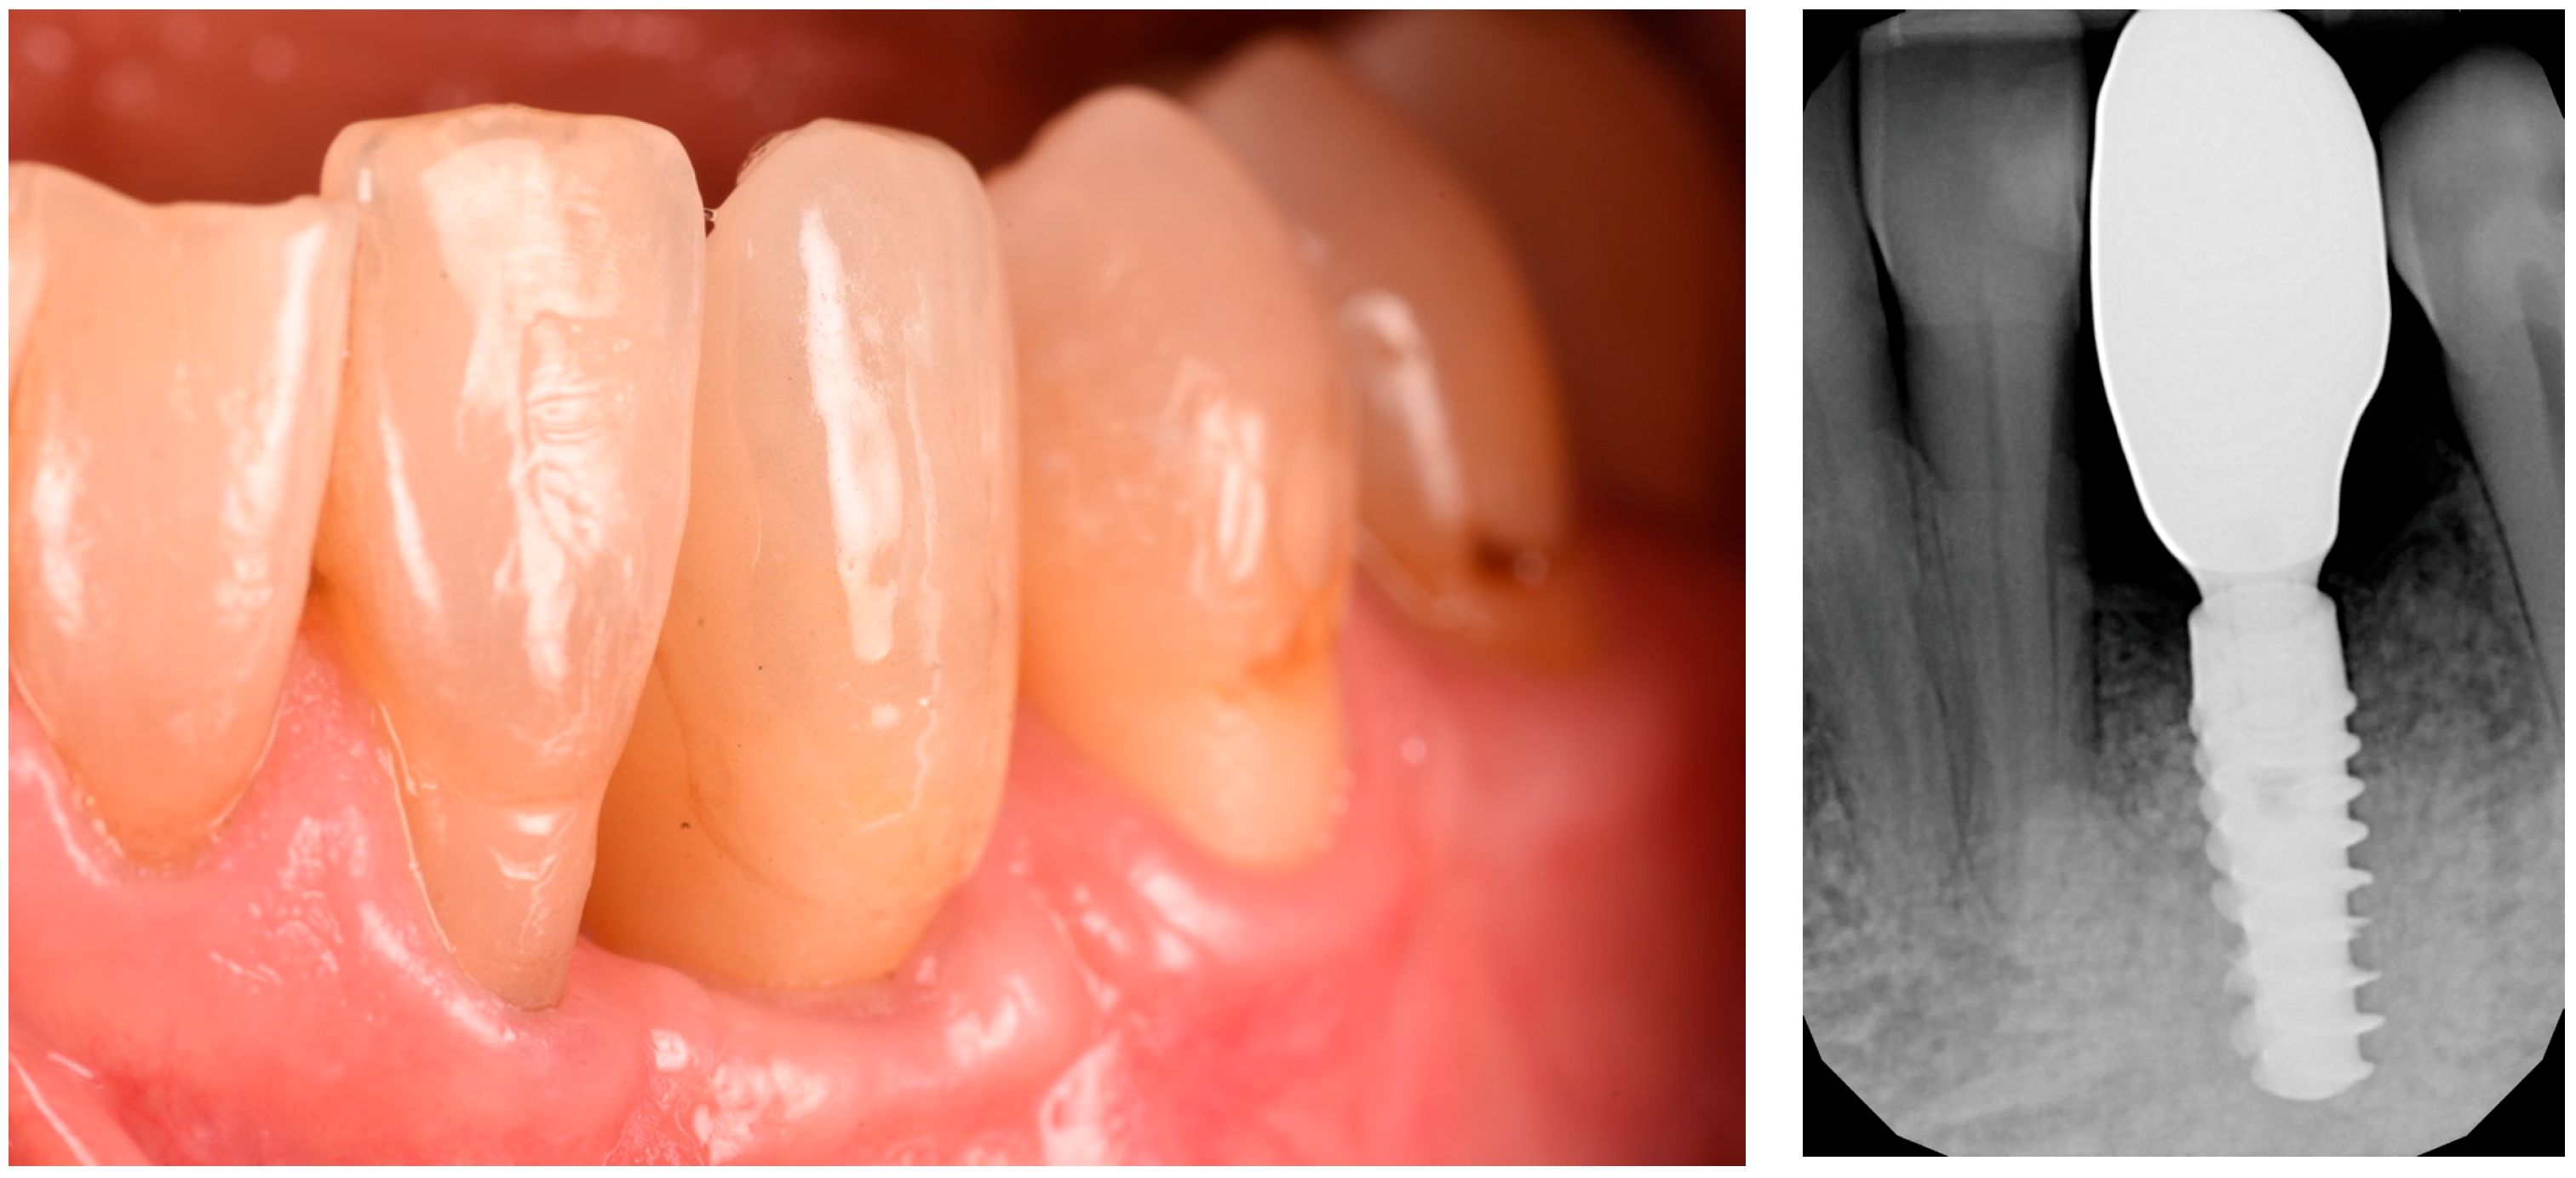

The extraction was performed at another practice while the patient was away for work, and it was conducted on an emergency basis (Figure 2). Three months post-extraction, the patient returned to our clinic, reporting a severe bone defect with significant loss of both the mesial bone peak and the buccal plate (Figure 3, Figure 4 and Figure 5). The proposed plan, which the patient accepted, involved performing a regenerative procedure using an FCS followed by delayed implant rehabilitation.

Figure 3. Frontal view of the bone defect three months post-extraction.

Figure 12. Soft tissue healing 8 months post-op and CBCT proving the shape of the ridge.